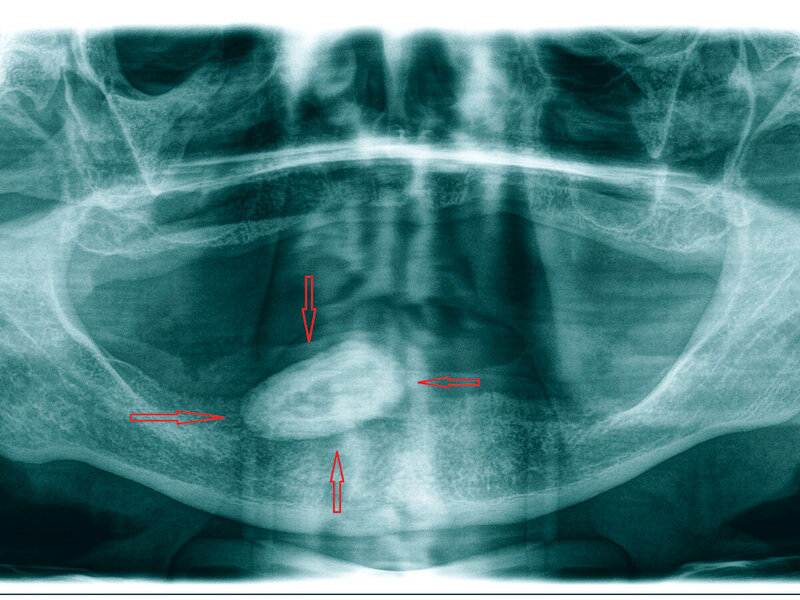

Die radiologische Diagnostik erfolgte mittels Panoramaschichtaufnahme (Abbildung 1). Auf dieser Röntgenaufnahme zeigte sich eine circa 27 mm x 15 mm große, hyperdense ovale Struktur, die sich über den rechten Unterkiefer projizierte.

Auf der Grundlage der Ergebnisse der klinischen und der radiologischen Untersuchung ergab sich mit allergrößter Wahrscheinlichkeit als Diagnose das Vorhandensein eines großen Sialolithen im Ductus submandibularis rechts. Überraschenderweise bestand trotz der außergewöhnlichen Steingröße keine klinisch relevante Beeinträchtigung des Speichelabflusses über den Ductus sublingualis. Auf näheres Befragen gab der Patient an, einmal vor einiger Zeit kurz anhaltende Schmerzen in dem Bereich gehabt zu haben.